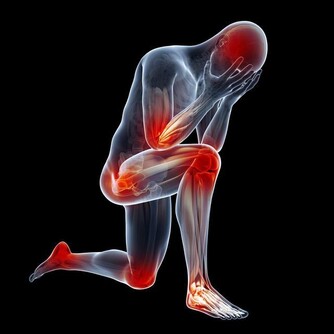

當一定量的內臟脂肪其實是人體必需的,因為內臟脂肪圍繞著人的臟器,對人的內臟起著支撐、穩定和保護的作用。然而,當內臟脂肪堆積過多時,一方面就會形成水桶腰、將軍肚等造成身材不美觀的問題;另一方面,內臟長期堆積過多脂肪會影響消化功能,導致內分泌紊亂,還增加了患高血脂、高血壓、脂肪肝等疾病的機會,下面就跟小編一起詳細瞭解吧!